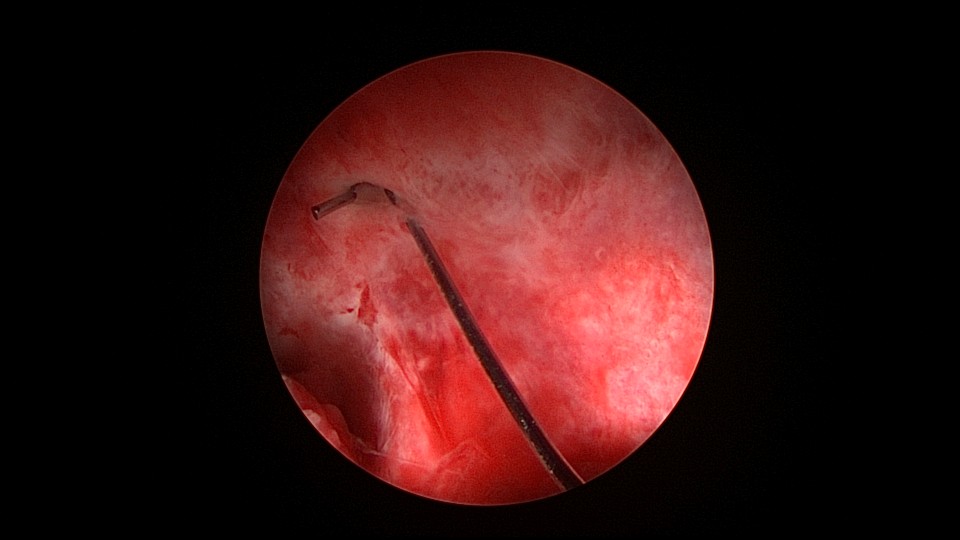

患者39岁,G6P1,顺产1次。2022年5月因输卵管间质部妊娠行宫腹腔镜手术(术前门诊医生诊断宫角妊娠),腹腔镜下行左侧输卵管间质部妊娠套扎开窗取胚术,术中见子宫腺肌症结节明显。2025年3月,严重痛经,皮下注射亮丙瑞林已3个周期,行经第6天,放置曼月乐并固定,拟行缝合固定,宫腔镜下缝合一针,牵拉确认缝合到肌层,推结时缝合处撕裂,拉出曼月乐,立即改为挂钩固定。先将不锈钢挂钩插入宫底肌层,4-0不可吸收线在曼月乐横臂中间套扎形成线圈,将曼月乐置入宫腔,异物钳夹持线圈挂到不锈钢挂钩里,原位固定曼月乐,退出宫腔镜,结束手术。2025年5月复查B超,节育环距宫底3cm,查看图片,线圈较大。节育环距宫底距离跟子宫大小、宫壁厚度、挂钩长度及线圈长度之和有关,保持这个距离不再延长即为手术成功。